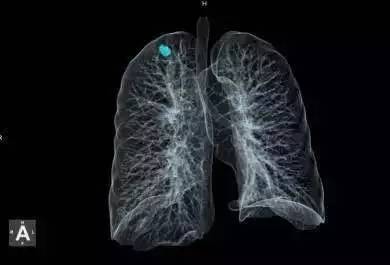

以肺癌早筛引擎为例,它深度融合了人工智能技术、基于卷积神经网络的深度学习技术以及云计算技术,实现了智能学习医生诊断全过程,自动识别肺结节并精准计算其量化参数,辅助决策,大幅提升诊断检出率与准确率,帮助患者早发现早治疗。经上海长征医院权威测评,这一智能影像辅助技术帮助工作经验在3年以下的医生将肺癌检出率提高了20%以上。